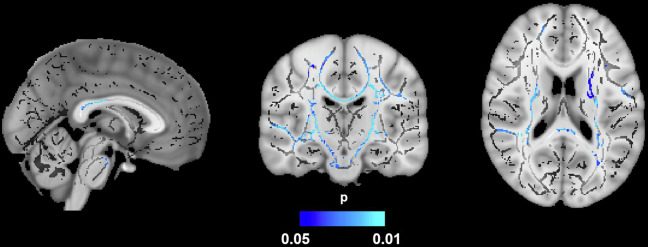

肥胖是痴呆的一个风险因素,它会造成慢性炎症状态,导致白质损伤。边缘密度成像(EDI)是一种新的技术,已经证明了量化WM变化的可靠性。30名肥胖和20名认知正常的非肥胖成年人接受了结构和扩散加权磁共振成像。内脏脂肪组织(VAT)和皮下脂肪组织(SAT)通过体素分析套件进行定量,分离脂肪组织和非脂肪组织的信号强度。扫描由管道(MaPPeRTrac)处理以生成EDI。在肥胖的参与者中,VAT/SAT比率和EDI之间存在负相关,而在非肥胖的参与者中没有看到。此外,男性的EDI比女性低。这项研究的结果表明,肥胖,通过WM损伤,可能增加痴呆的风险,性别是一个潜在的差异因素。EDI在描述肥胖和痴呆的神经病理学方面显示出了希望。

Obesity is a risk factor for dementia, creating a chronic inflammatory state that results in white matter (WM) injury. Edge density imaging (EDI) is a novel technique that has demonstrated reliability in quantifying WM changes. Thirty obese and 20 non-obese cognitively normal adults underwent structural and diffusion-weighted magnetic resonance imaging. Visceral adipose tissue (VAT) and subcutaneous adipose tissue (SAT) were quantified via VOXel Analysis Suite by separating signal intensities of adipose and non-adipose tissue. Scans were processed by a pipeline (MaPPeRTrac) to generate EDI. Among obese participants, there was a negative association between the VAT/SAT ratio and EDI, which was not seen among non-obese participants. Additionally, males had decreased EDI compared to females. The results of this study suggest that obesity, through WM damage, may confer increased risk of dementia, with sex as a potential differential factor. EDI demonstrates promise in delineating the neuropathology of obesity and dementia.